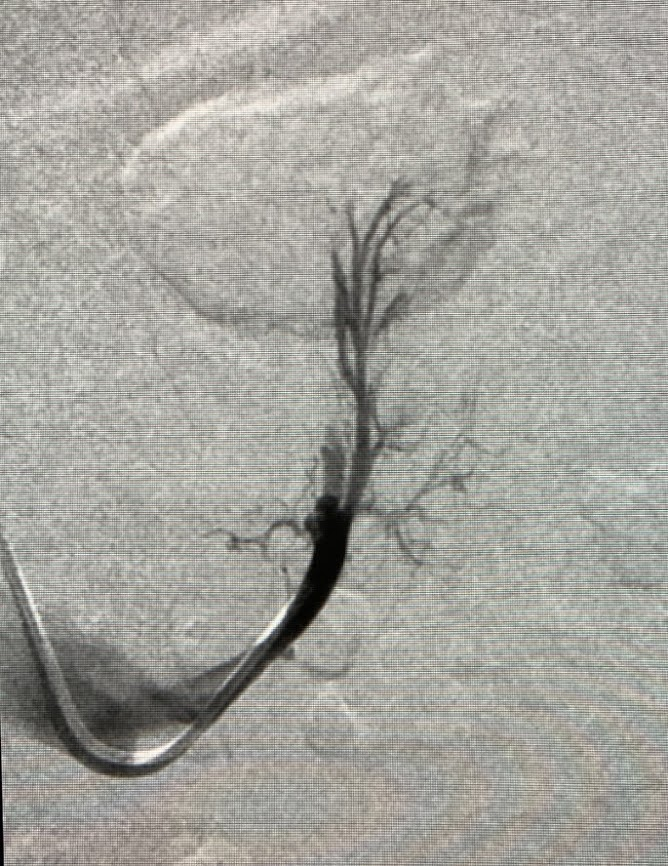

超選択的副腎静脈サンプリングは通常の左右の副腎中心静脈に加え、さらに細い支脈に入れ分けて採血を行う検査です。原発性アルドステロン症の局在診断(片側性/両側性など)と治療方針決定(手術療法か薬物療法か)のために行います。一般的に右副腎静脈採血が難しく、左副腎静脈採血は簡単とされますが、実際には支脈レベルの解剖学的変異から左副腎静脈から採血に困ることがしばしば経験されます。そのため、過去の血管撮影画像を後方視的に振り返り、左副腎静脈の支脈レベルでの血管解剖について分類しました。